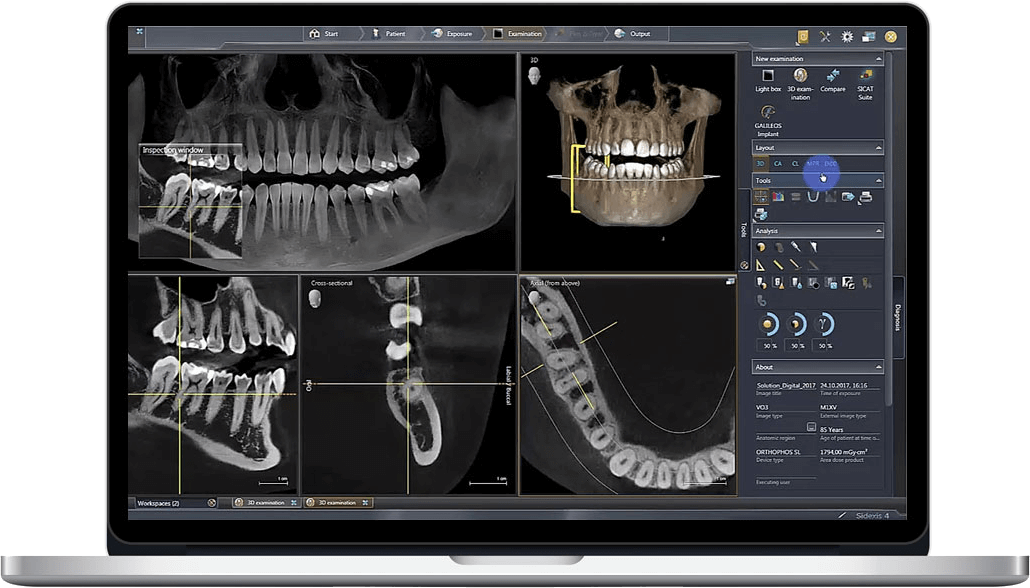

1. Photon-Counting Spectral Imaging (Engineering Principle)

Modern CBCT systems deploy cadmium telluride (CdTe) detectors with pulse-height analysis circuits that discriminate X-ray photons by energy level. This enables:

- Material decomposition: Simultaneous acquisition of 4-6 energy bins allows differentiation of hydroxyapatite (bone), amalgam, titanium implants, and soft tissue via basis material decomposition algorithms. Eliminates need for dual-energy scans.

- Beam hardening correction: Pre-scan spectral calibration maps attenuation coefficients to material composition, reducing cupping artifacts by 78% (per NIST phantom validation).

3. Multi-Modal Registration Architecture

CBCT integration with intraoral scanners (structured light/laser triangulation) now leverages:

- Featureless registration: Differentiable rendering pipelines that minimize photometric loss between CBCT-derived surface projections and optical scans

CBCT (Cone Beam Computed Tomography) has evolved from a diagnostic tool to the structural backbone of precision digital dentistry. This review analyzes its critical integration points in chairside and lab workflows, CAD software interoperability challenges, and the strategic imperative of open architecture systems. 2026 marks the inflection point where CBCT-driven workflows directly determine clinical outcomes, production efficiency, and service scalability.

CBCT Integration: Chairside & Lab Workflow Deconstruction

Modern CBCT integration transcends simple image acquisition. It requires spatially anchored data pipelines that maintain anatomical fidelity across software ecosystems. Key integration phases: